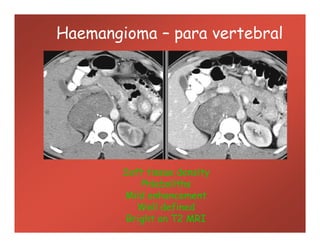

Haemangioma – para vertebral

Soft tissue density

Phleboliths

Mild enhancement

Well defined

Bright on T2 MRI